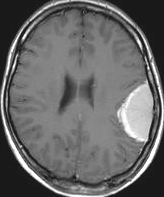

最も見やすいのが,ガドリニウム造影剤を注射して撮影するものです。一般的に髄膜腫は造影剤で白く映し出されます。この腫瘍は左脳側にあります。MRIの軸面という輪切りの写真では左右が逆になりますから注意してください。脳を下から見た図になっています。MRIはいろいろな方向から腫瘍を見ることができますが,右は冠状断という正面から見た図です。よく見ると腫瘍の上と下のはじっこに線状に糸を引いたように造影される部分があります。これをテールサイン(しっぽのサイン)といいます。腫瘍が硬膜に沿って延びている可能性があることを示しています。